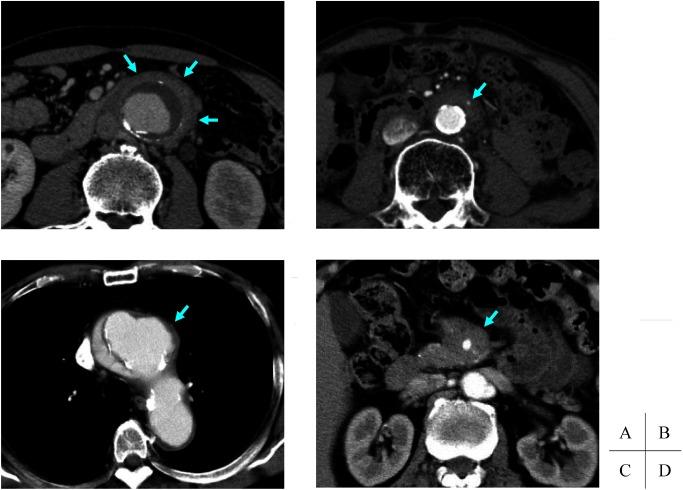

Immunoglobulin G4-related diseases (IgG4-RD) are systemic inflammatory conditions, characterized by high serum IgG4 concentrations, and pathologically IgG4-positive plasmacytes infiltrations and storiform fibrosis. We described IgG4-related inflammatory abdominal aortic aneurysm in 2008, and revealed the existence of vascular lesions. IgG4-related vascular lesions frequently occur in the aorta and branching medium-sized arteries with or without aneurysmal change. The inflammatory lesion mainly involves in the adventitia, indicating remarkable adventitial fibrous thickening with infiltration of inflammatory cells. Clinical symptoms associated with IgG4-related vascular lesions might be fever, abdominal pain, hydronephrosis, or few subjective symptoms. Comprehensive diagnostic criteria is applied according to image findings of thickening lesions, high serum IgG4 levels, and histopathological findings. As a treatment, open surgical repair or endovascular aneurysm repair is performed for the aneurysmal cases, and steroid administration is used for the cases with strong inflammation. This disease can lead to a lethal situation due to the rupture following aneurysmal formation, thus special attention is needed unlike IgG4-RD occupying in the other organs. (This is a translation of Jpn J Vasc Surg 2017; 26: 129-134.).

免疫球蛋白G4相关疾病(IgG4-RD)是一种全身性炎症性疾病,其特征为血清IgG4浓度升高,病理表现为IgG4阳性浆细胞浸润和席纹状纤维化。我们在2008年描述了IgG4相关的炎性腹主动脉瘤,并揭示了血管病变的存在。IgG4相关血管病变常发生于主动脉和分支中等大小动脉,可伴有或不伴有动脉瘤样改变。炎性病变主要累及外膜,表现为外膜显著纤维增厚并伴有炎性细胞浸润。与IgG4相关血管病变相关的临床症状可能为发热、腹痛、肾积水或仅有少数主观症状。根据增厚病变的影像学表现、血清IgG4水平升高及组织病理学表现应用综合诊断标准。对于动脉瘤病例,治疗方法为开放手术修复或血管腔内动脉瘤修复,对于炎症较重的病例则使用类固醇药物治疗。由于动脉瘤形成后破裂可导致致命情况,因此与占据其他器官的IgG4-RD不同,对此病需要特别关注。(本文翻译自《日本血管外科学杂志》2017年;26: 129 - 134.)